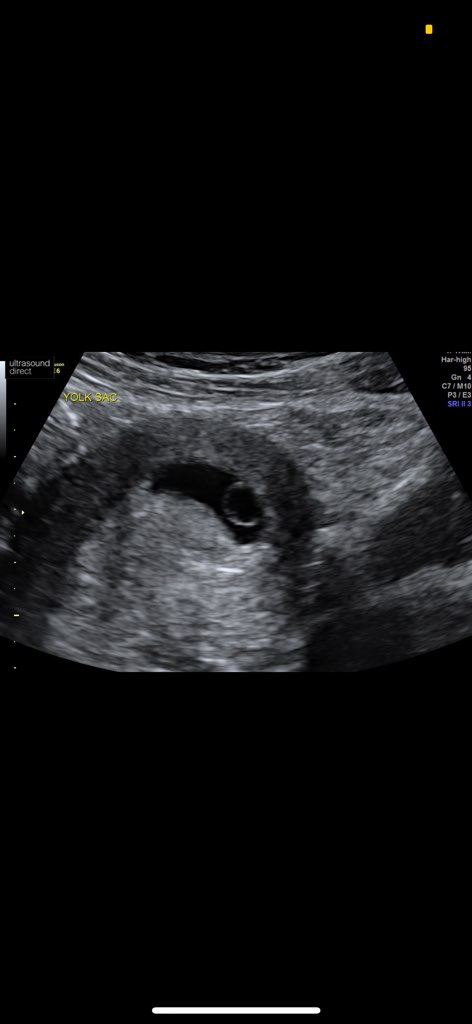

To bardzo normalne ja na te bóle mam zalecenie żeby brać nospe albo spazmoline żeby macica się rozkurczała. Co do mdłości to od czasu do czasu mam lekkie ale nie jest tak żebym nie miała apetytu albo wymiotowała.Hej dziewczyny, czy te bóle podbrzusza już od kilku dni (około 5ciu) to normalne w 5tc? Kluja mnie jajniki, raz lewy raz prawy, spać w nocy nie mogę ale żadnych mdłości nie mam. Jestem po inseminacji robiłam 3 razy bete. Wyniki 44/260/903. W najbliższy piątek mam Gin a tak strasznie się stresuje co będzie... Dodam że jestem po 3 biochemicznych![]()

też idę 6+0, jestem po biochemie, byłam też w 4+0, ale tylko po leki poszłam .Ja idę w 6+0 do gina aby zobaczyć czy pęcherzyk jest na miejscu. Jestem po jednym cp, a przy takim tyg powinno być już wiadome![]()